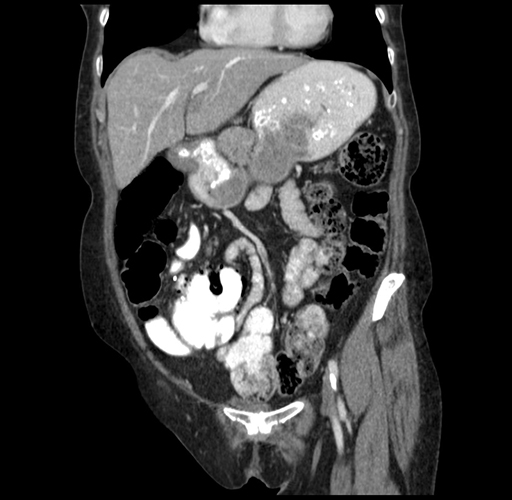

Pre-Chemo: Coronal Venous